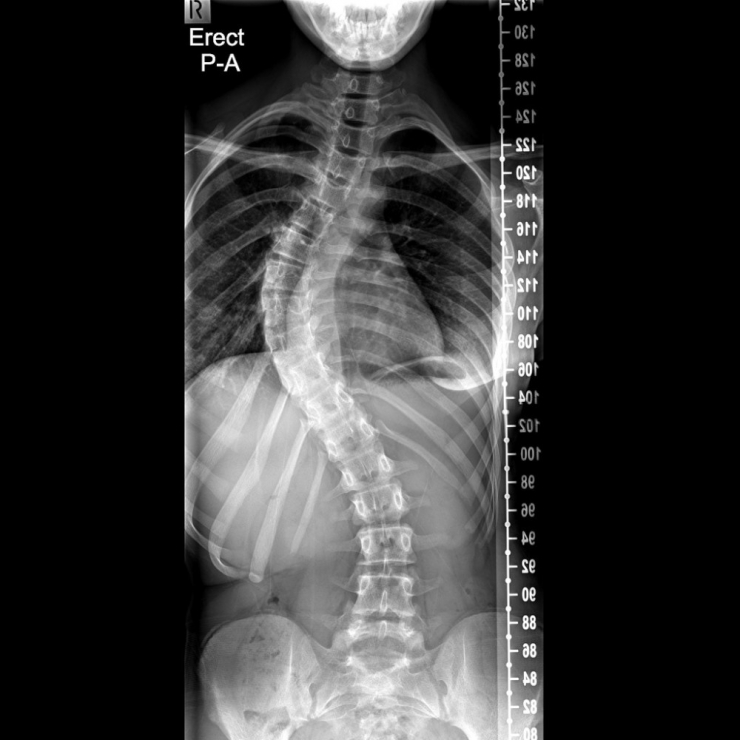

Başın bir tarafa doğru eğimli olması, göğüs kafesinde asimetri, kürek kemiklerinden birinin diğerine göre daha tümsek şeklinde olması, kalçalar ve omuz seviyeleri eşit olmaması, bacak eşitliklerinin aynı olmadığından şikayet edilmesi gibi durumlar skolyoz habercisi olabileceğinin beliren Prof. Dr. Bahadır, "Skolyozun ilerleyişi kişinin yaşı, cinsiyeti, eğriliğin tipi ve büyüklüğüyle farklılık gösterir. Skolyoz kız çocuklarında daha fazla görülmektedir. Hızlı büyümenin olduğu ergenlikte eğrilik hızlı ilerler. Skolyozun tanısı için dikkatli bir muayene ve basit bir röntgen filmi yeterlidir. Yalnız her eğrilik skolyoz değildir. Skolyozda vertebra eğimi 10 derecenin üzerinde olmaldır. Bunun altındaki eğrilikler skolyoz olarak sınıflandırılmaz" şeklinde konuştu.

Skolyozda erken tanının çok önemli olduğunu vurgulayan Fizik Tedavi ve Rehabilitasyon Uzmanı Prof. Dr. Cengiz Bahadır, "40-50 dereceye ulaşmış skolyozlar genelde cerrahi olarak tedavi edildiğinden bu aşamalara gelmeden tanı konması önemlidir. Erken tanı ile tedavi çok daha başarılı olmaktadır. Erken yaşlarda özelikle ergenlik öncesi dönemde eğrilik fazla ise kişiye özel korse kullanılabilir. Hasta bu korseyi günün büyük bölümünde kullanır. Skolyozun tedavisi her zaman özel egzersiz programları ile yapılmaktadır. Bunlardan en önemlisi olan Schroth methodu, kendisi de skolyoz olan Katherina Schroth tarafından geliştirilmiştir. 1921 yılında Schroth tarafından uygulanmaya başlayan üç boyutlu egzersiz tedavisi günümüzde gelişerek ve başta Almanya olmak üzere birçok ülkede yaygınlaşarak uygulanmaya devam edilmektedir. Egzersizler özellikle skolyozlu omurganın konkav tarafına nefes alınması ve ayna karşısında kişinin deformitelerini düzeltme temeline dayanır. Kişi ayna karşısında öğretilen duruşlar ve egzersizler ile duruş kontrolünü sağlayarak, bu düzgünlüğü günlük yaşamında nasıl devam ettireceğini öğrenir. Günlük yaşam alışkanlıklarının değiştirilmesi, kamburluk ve çukurlukların düzeltilmesi, mobilizasyon ve egzersiz bu tekniğin temel elementleridir. Egzersizler nefes temelli olduğu için yapılan çalışmalarda akciğer kapasitesinde iyileşme, eğrilikte azalma ve gövde duruşunda düzelme görülmüştür" ifadelerini kullandı.